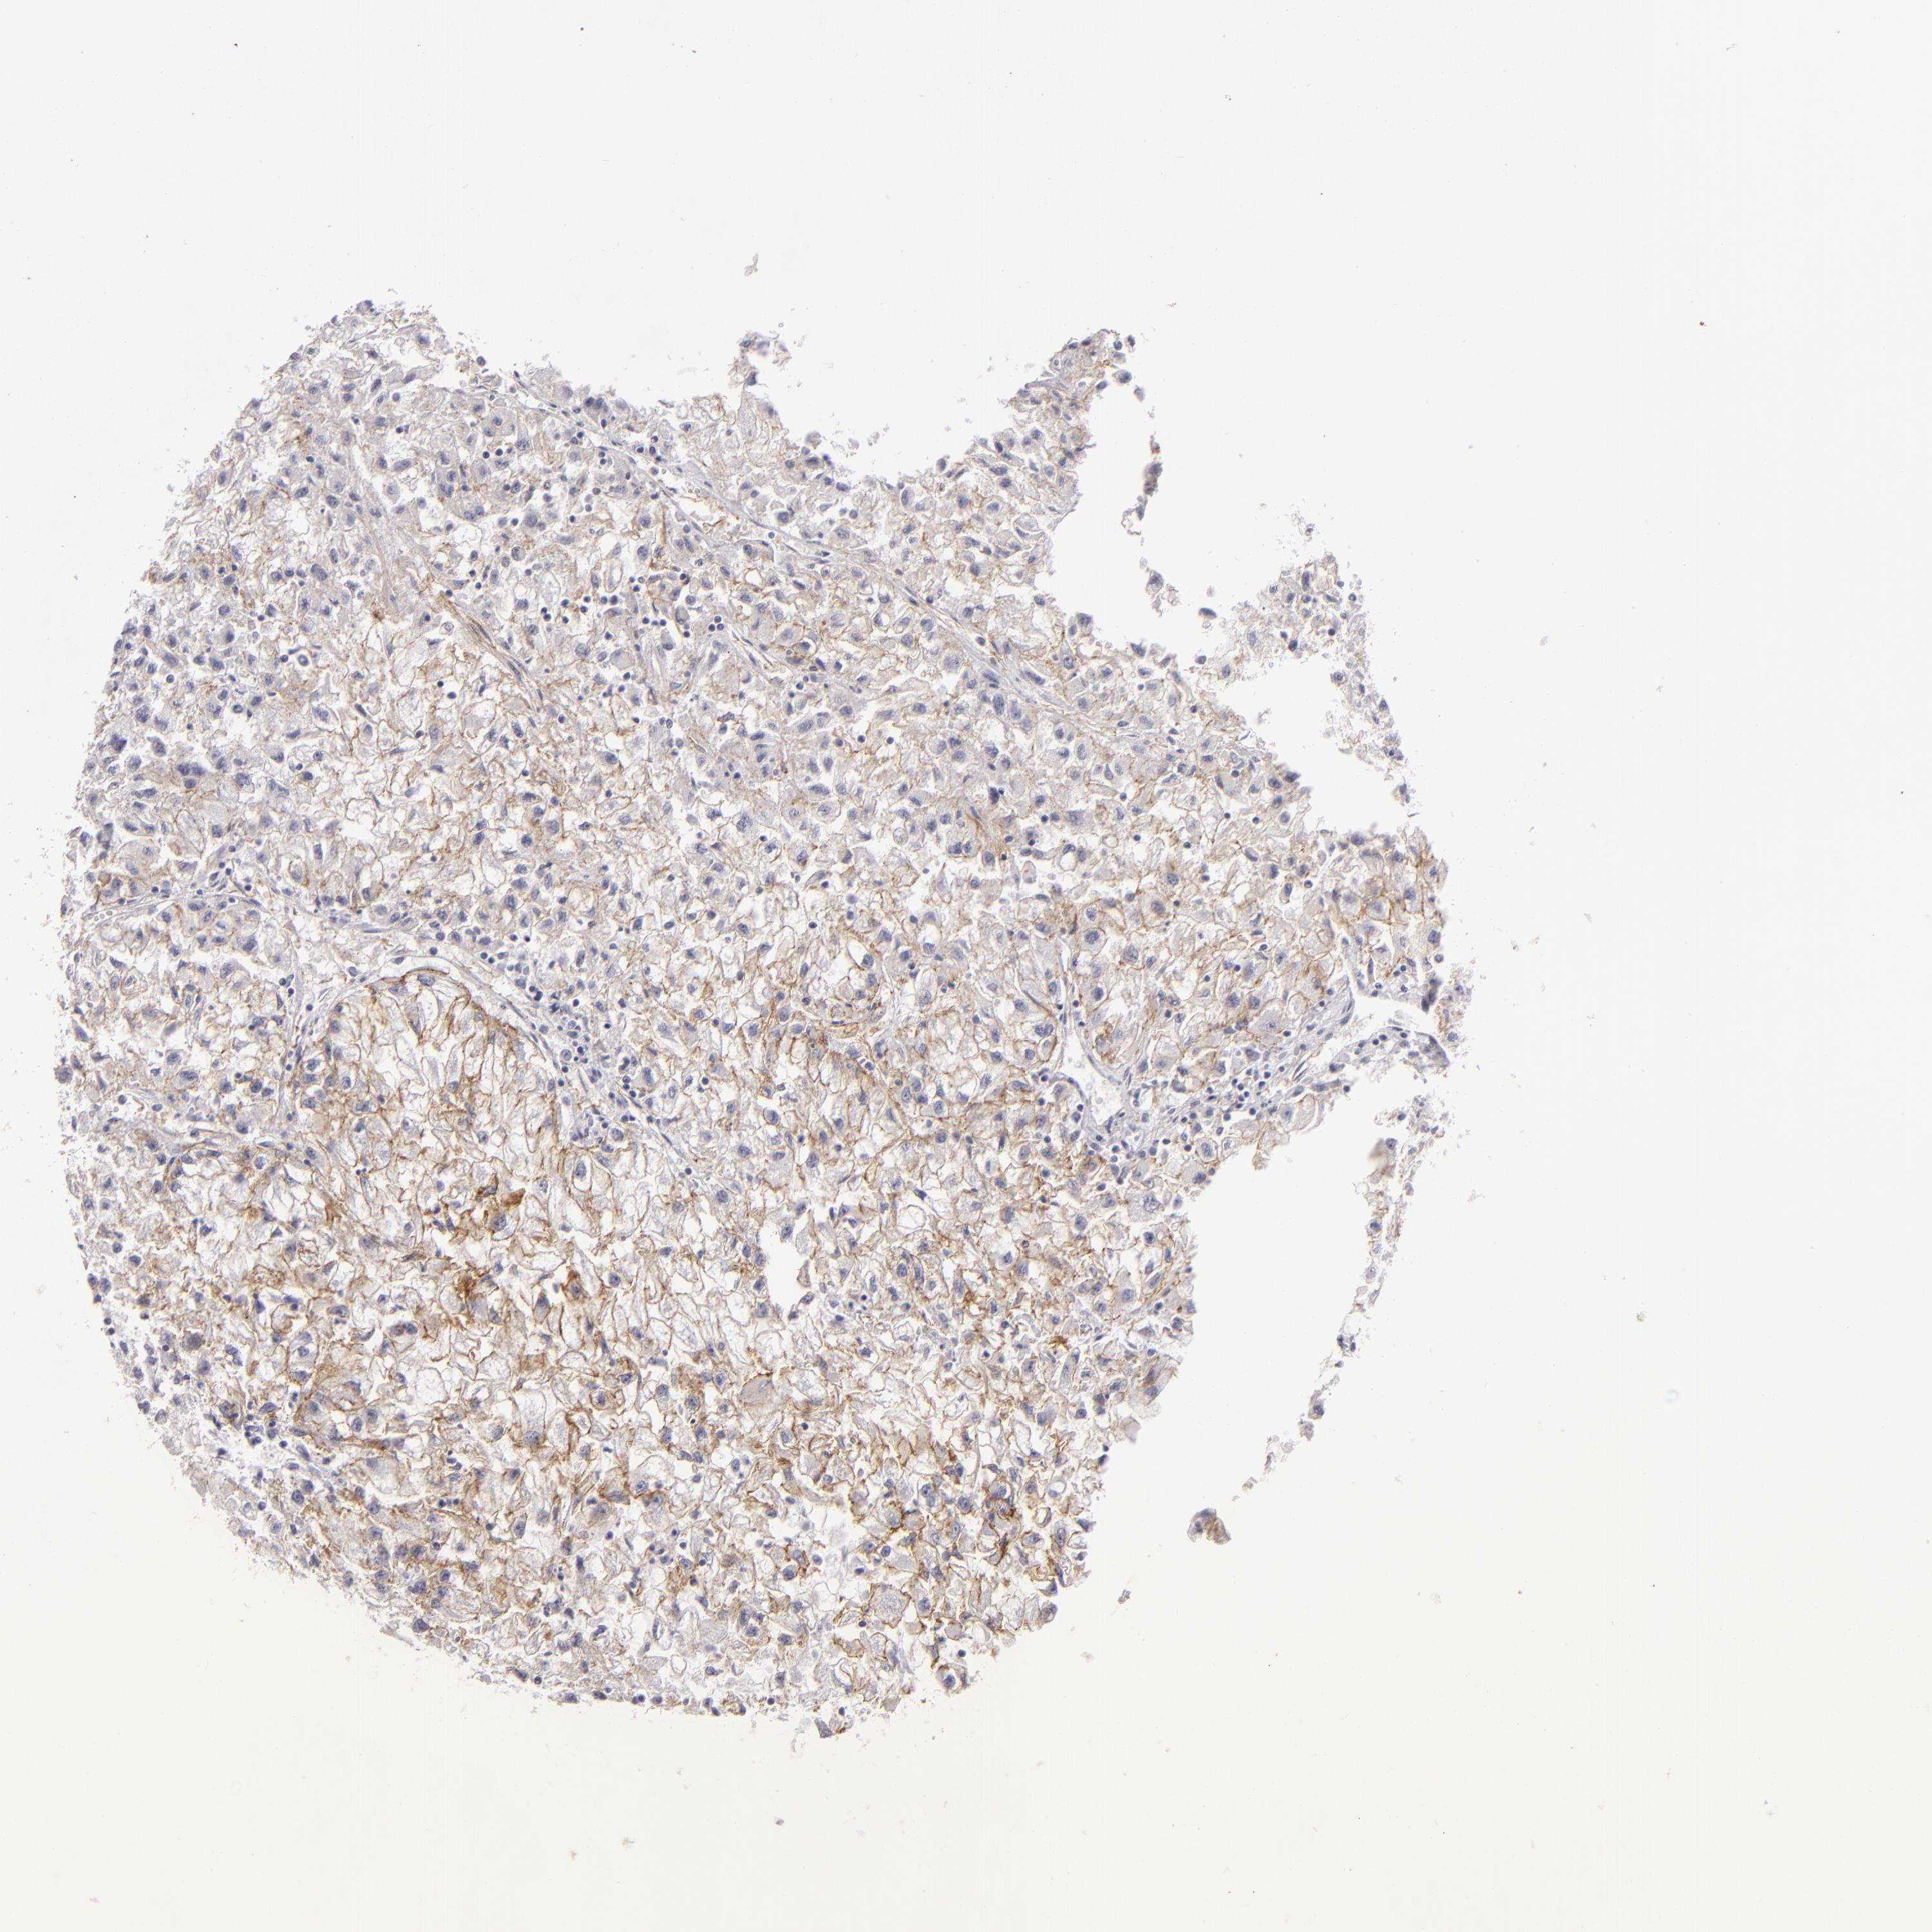

KIDNEY RENAL CLEAR CELL CARCINOMA (VALIDATION) - Interactive survival scatter ploti

The Survival Scatter plot shows the clinical status (i.e. dead or alive) for all individuals in the patient cohort, based on the same data that underlies the corresponding Kaplan-Meier plots. Patients that are alive at last time for follow-up are shown in blue and patients who have died during the study are shown in red.

The x-axis shows the expression levels (FPKM) of the investigated gene in the tumor tissue at the time of diagnosis. The y-axis shows the follow-up time after diagnosis (years). Both axes are complimented with kernel density curves demonstrating the data density over the axes. The top density plot shows the expression levels (FPKM) distribution among dead (red) and alive patients (blue). The right density plot shows the data density of the survived years of dead patients with high and low expression levels respectively, stratified using the cutoff indicated by the vertical dashed line through the Survival Scatter plot. This cutoff is automatically defined based on the FPKM cutoff that minimizes the p-score. The cutoff can be changed by dragging the vertical line or by entering a cutoff value in the square labeled "Current cut-off".

Under the Survival Scatter plot the p-score landscape (black curve; left axis) is shown together with dead median separation (red curve; right axis). Dead median separation is the difference in median mRNA expression between patients who have died with high and low expression, respectively. It is calculated as follows: median FPKM expression of dead patients with high expression - median FPKM expression of dead patients with low expression. This is intended to aid the user in visually exploring custom cutoffs and the associated p-scores and dead median separation.

Individual patient data is displayed and can be filtered by clicking on one or more of the category buttons on the top of the page. Categories describing expression level and patient information include: high, low, alive, dead, female, male and tumor stages. The scale of the x-axis can be toggled between linear and log-scale by clicking on the "x log" button. Mouse-over function shows TCGA ID, patient information and mRNA expression (FPKM) for each patient.

& Survival analysisi

Kaplan-Meier plots summarize results from analysis of correlation between mRNA expression level and patient survival. Patients were divided based on level of expression into one of the two groups "low" (under cut off) or "high" (over cut off). X-axis shows time for survival (years) and y-axis shows the probability of survival, where 1.0 corresponds to 100 percent.

JUP is validated prognostic, high expression is favorable in Kidney Renal Clear Cell Carcinoma (validation)

Best expression cut offi

Based on the FPKM value of each gene, patients were classified into two groups and association between prognosis (survival) and gene expression (FPKM) was examined. The best expression cut-off refers the FPKM value that yields maximal difference with regard to survival between the two groups at the lowest log-rank P-value. Best expression cut-off was selected based on survival analysis .

When clicking on this number, the vertical dashed line indicating cut-off, the interactive survival plot, and the Kaplan-Meier curve will be adjusted to show results based on the best expression cut-off.

: 90.21

P scorei

Log-rank P value for Kaplan-Meier plot showing results from analysis of correlation between mRNA expression level and patient survival.

N/A

5-year survival highi

5-year survival for patients with higher expression than the expression cutoff.

For melanoma and glioma, 3-year survival is shown.

5-year survival lowi

5-year survival for patients with lower expression than the expression cutoff.

TCGA RNA samplesi

RNA-seq data is reported as average FPKM (number Fragments Per Kilobase of exon per Million reads), generated by the The Cancer Genome Atlas (TCGA) .

Normal distribution across the dataset is visualized with box plots, shown as median and 25th and 75th percentiles. Points are displayed as outliers if they are above or below 1.5 times the interquartile range. FPKM values of the individual samples are presented next to the box plot.

Average pTPM 89.2

Number of samples 100